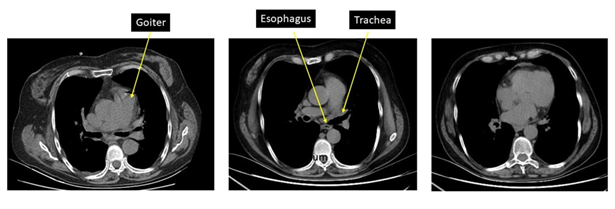

(figure 6).

Figure 6: ct with goiter that maintains undamaged tracheal lumen.